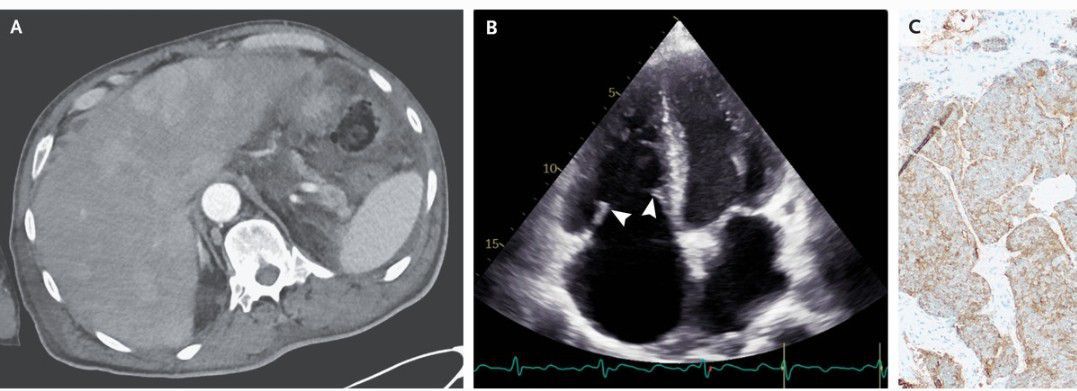

A 67-year-old man presented to the emergency department with a 1-month history of dyspnea and diarrhea and a 1-day history of abdominal pain. On physical examination, there was jugular venous distention with prominent V waves, a holosystolic murmur at the left lower sternal border, diffuse wheezing, and leg edema, but no flushing. Computed tomography of the abdomen showed thickening of the cecum and ascending colon, as well as numerous contrast-enhancing liver lesions (Panel A). Transthoracic echocardiography showed thickened, stiff tricuspid-valve leaflets with restricted mobility (Panel B [arrowheads] and Video 1) and severe tricuspid regurgitation (Video 2). The pulmonic valve was not clearly seen, but severe pulmonic regurgitation was noted. The 24-hour urinary 5-hydroxyindoleacetic acid level was 174 mg (reference value, <15). A biopsy of the liver mass showed a neuroendocrine tumor (Panel C, chromogranin A stain). A diagnosis of carcinoid syndrome with carcinoid heart disease in the context of a metastatic neuroendocrine tumor from a likely colonic primary site was made. Carcinoid heart disease occurs when high levels of vasoactive substances released from liver neuroendocrine metastases flow to the right heart and cause endocardial damage. Treatment with diuretics and octreotide was initiated, but the patient then opted for hospice care and died 1 month later.